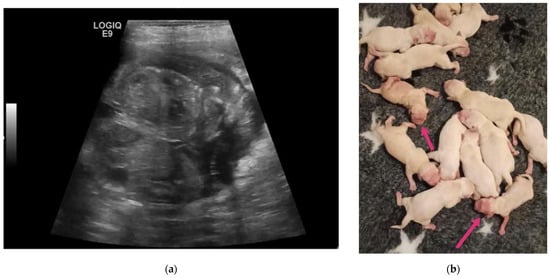

| 1F 2F | 6-year-old Birman female cat | 45 and 52 | 5 | Two pairs of monochorionic twins, morphologically comparable to the other foetus. | Natural delivery without assistance, three kitten stillborn. | One kitten dead for sepsis after 7 days. |

| 3F | 4-year-old European female cat | 50 | 4 | Monochorionic twins, morphologically comparable to the other foetuses. | Natural delivery without assistance, entangled neonates’ umbilical cords. | |